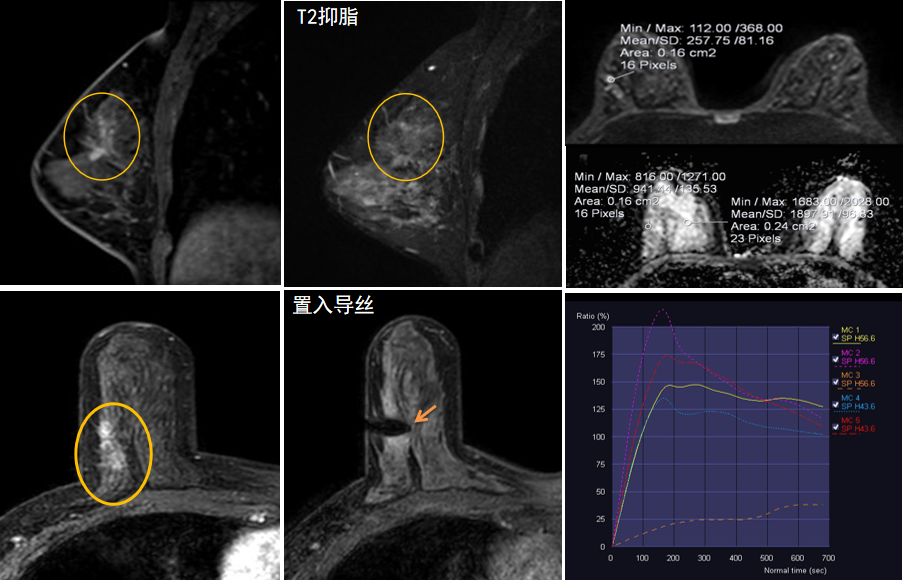

今年45歲的某女士,兩個(gè)月前行超聲檢查發(fā)現(xiàn)右乳結(jié)節(jié),乳腺X線攝影檢查提示右乳外上象限局部腺體結(jié)構(gòu)扭曲并簇狀無(wú)定形鈣化,為了進(jìn)一步評(píng)估病變性質(zhì)并確定范圍進(jìn)行了乳腺M(fèi)R平掃 DWI 增強(qiáng)的檢查,經(jīng)MR評(píng)估發(fā)現(xiàn)右乳病變范圍較廣,評(píng)估為BI-RADS 4類(lèi)可疑病變,需要取得病理學(xué)結(jié)果。

西安國(guó)際醫(yī)學(xué)中心醫(yī)院影像診療中心陳寶瑩主任團(tuán)隊(duì)有著十余年影像引導(dǎo)下乳腺介入診療的經(jīng)驗(yàn),借助醫(yī)院高精尖的MR平臺(tái),成為西北首個(gè)全面展開(kāi)MR引導(dǎo)下各項(xiàng)乳腺介入診療技術(shù)的團(tuán)隊(duì),能夠?qū)Τ暭叭橄賆線無(wú)法顯示或顯示不清的病變進(jìn)行MR引導(dǎo)下的導(dǎo)絲定位、穿刺活檢及真空輔助旋切。

陳寶瑩主任及其帶領(lǐng)的MR介入診療小組詳細(xì)詢問(wèn)了病情,分析了患者資料,并與患者和臨床醫(yī)生進(jìn)行了充分溝通,確定于手術(shù)前為患者實(shí)施MR引導(dǎo)下的病變穿刺導(dǎo)絲定位和體表范圍確定。手術(shù)前陳寶瑩主任帶領(lǐng)聶品醫(yī)師、馬小偉技師、韓愛(ài)萍護(hù)士長(zhǎng)等MR介入診療小組成員,借助MR高清的圖像顯示和定位系統(tǒng),確定病變范圍,精準(zhǔn)穿刺置入定位導(dǎo)絲,并準(zhǔn)確標(biāo)記出病變體表范圍,整個(gè)過(guò)程患者無(wú)任何不適。在定位導(dǎo)絲和體表范圍標(biāo)記的輔助下,甲乳外科劉曉敏主任精準(zhǔn)切除了病變,解除了患者的后顧之憂。

國(guó)內(nèi)外指南均建議40歲以上的女性每年行一次雙乳X線攝影(鉬靶)檢查,以篩查乳腺癌。對(duì)于乳腺癌高危人群40歲以前即建議開(kāi)始乳腺癌篩查,除了進(jìn)行乳腺X線攝影(鉬靶)篩查外需要補(bǔ)充MR檢查,MR檢查敏感性最高,能夠發(fā)現(xiàn)大量X線攝影和超聲檢查陰性的可疑病變,基于多模態(tài)、多參數(shù)的結(jié)構(gòu)和功能成像的基礎(chǔ)上,MR能夠精準(zhǔn)顯示病變位置、范圍以及病變內(nèi)的活性區(qū)域,MR引導(dǎo)下的介入診療不但解決了僅在MR顯示的病變的處置難題,而且能夠精準(zhǔn)定位活性區(qū)域,保證了定位、活檢及旋切的準(zhǔn)確性。